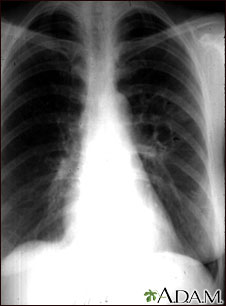

This chest x-ray shows the affects of a fungal infection, coccidioidomycosis. In the middle of the left lung, there are multiple, thin-walled cavities (seen as light areas) with a diameter of 2 to 4 centimeters. To the side of these light areas are patchy light areas with irregular and poorly defined borders.

Other diseases that may explain these x-ray findings include lung abscesses, chronic pulmonary tuberculosis, chronic pulmonary histoplasmosis, and others.